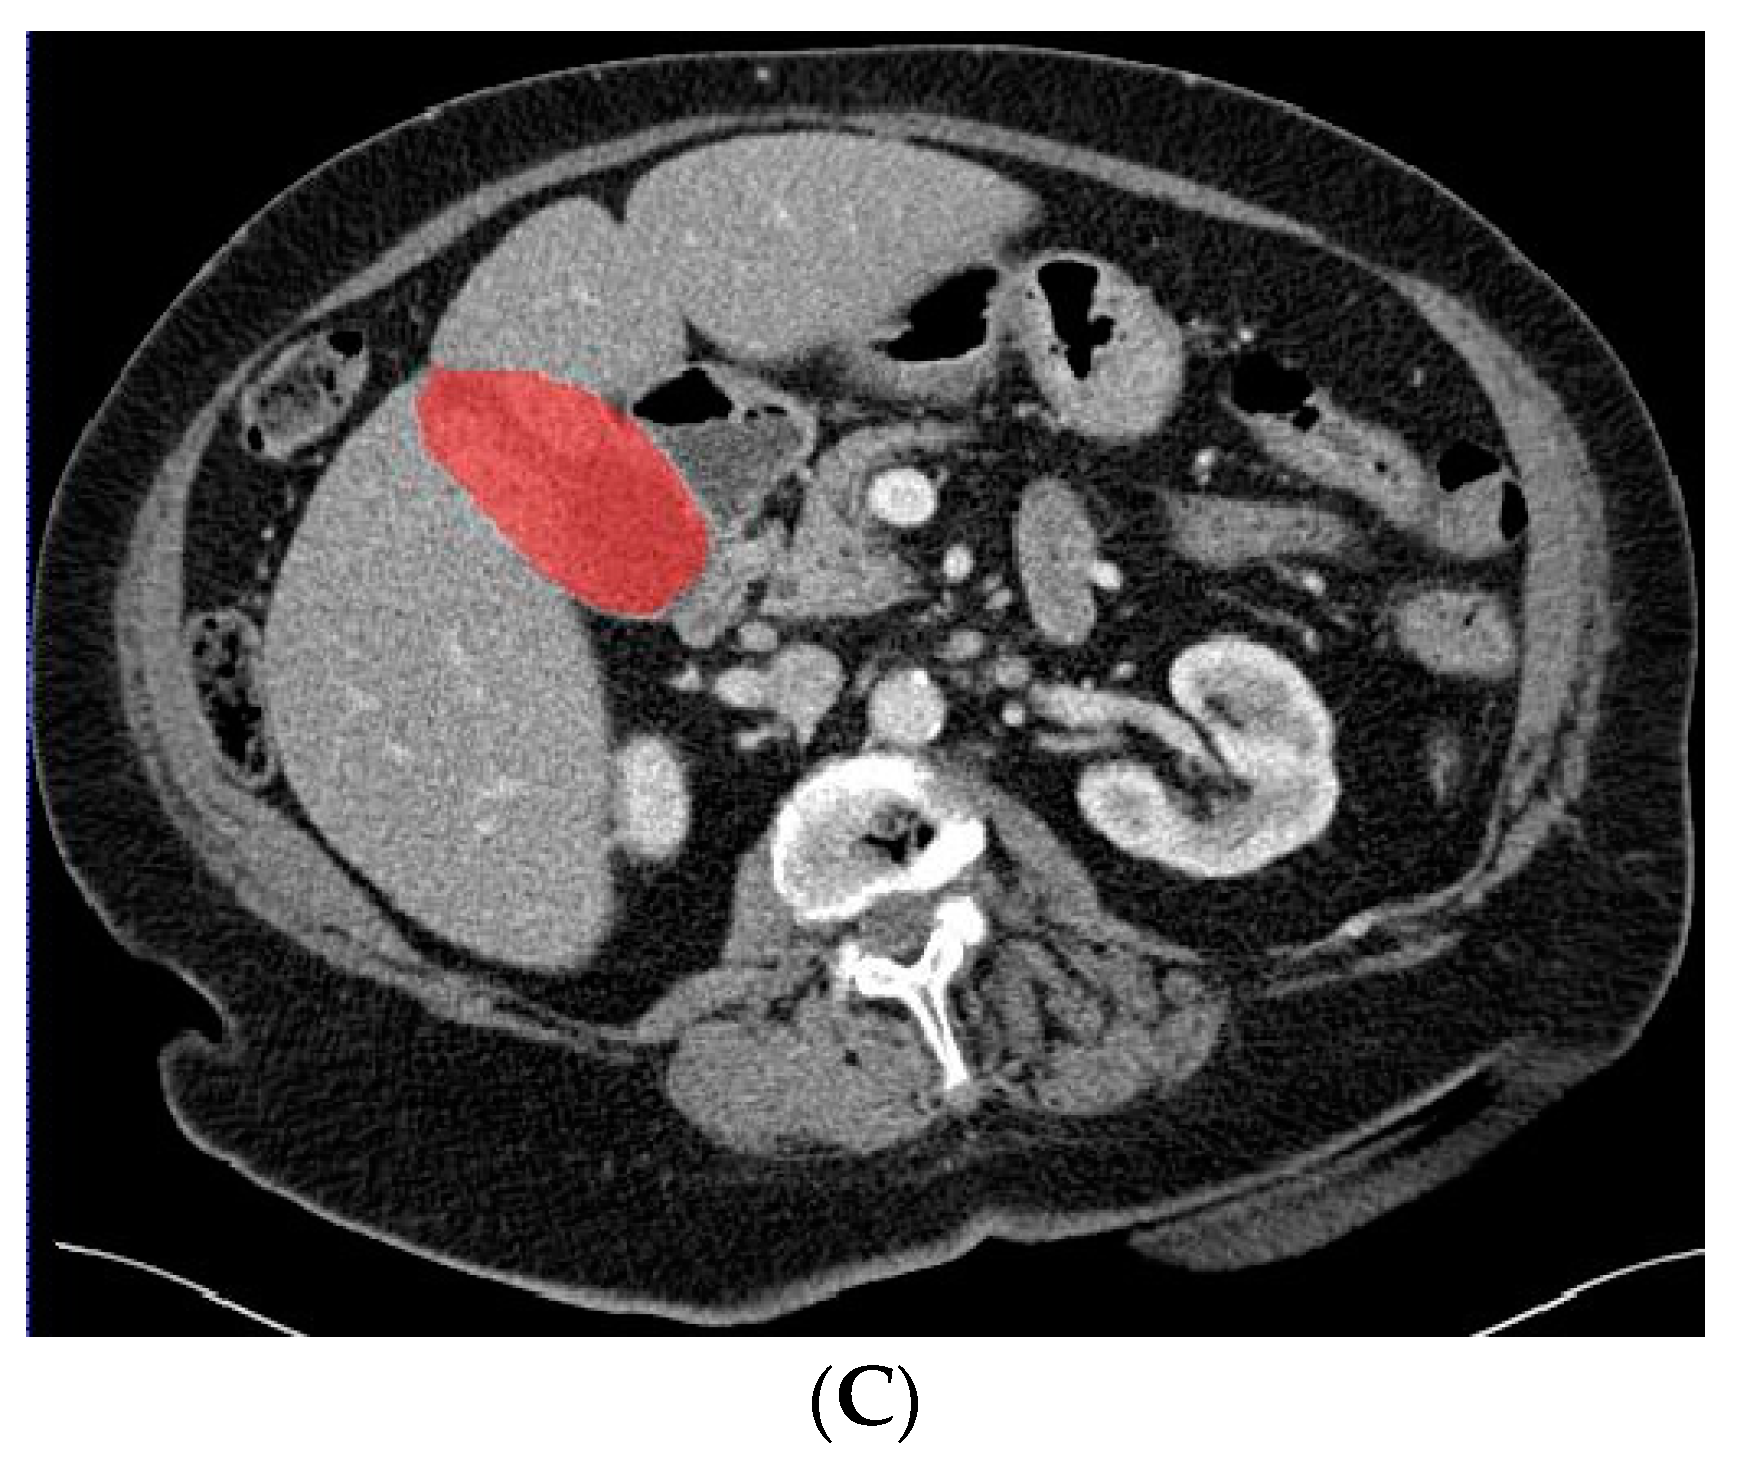

2.3. Deep Learning Model Based on Gallbladder and Liver Parenchyma

In a previous study, the suspicion of invasion of adjacent liver parenchyma was observed to be positively related to GBC [5]. Therefore, in addition to using only the gallbladder on CT images when training the deep learning model, a separate analysis was performed to investigate whether the combination of the gallbladder and adjacent liver parenchyma could increase the performance of the deep learning model when differentiating between GBC and benign gallbladder disease. The segmentation of a 2 cm rim of liver parenchyma adjacent to the gallbladder was automatically generated and adjusted by an experienced abdominal radiologist if necessary. The adjacent liver parenchyma was combined with the segmented gallbladder as training data for the deep learning model. Figure 4 shows examples of input CT images with segmentation of both the gallbladder and 2 cm of adjacent liver parenchyma. The deep learning model based on the combination of the gallbladder and adjacent liver parenchyma was trained and tested by the same methodology as described for the model solely based on the gallbladder.